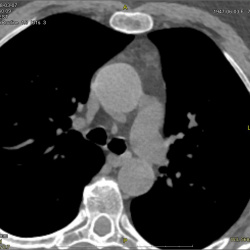

КТ 2х срезовый.

Женщина 80 лет, направлена с ДЗ гемипарез... в брюшной полости пальпируется крупное образование. Справа, паравертебрально, какое мягкотканное образование. Интересуют...